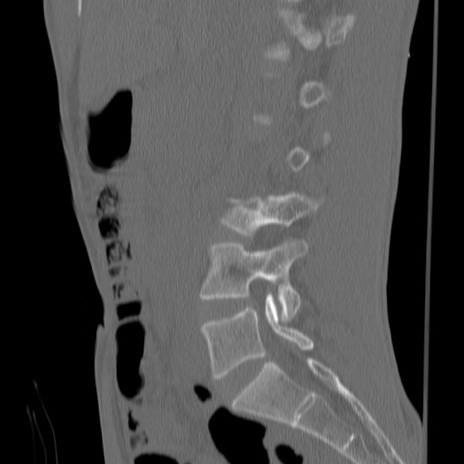

症例3 腰椎CT(矢状断像)

【症例】30歳代男性

【主訴】腰痛

【現病歴】本日旅行先で観光中に、友人と衝突し転倒し受傷。

【身体所見】麻痺なし、右下腿内側前面外側、左下腿内側に知覚鈍麻・しびれ

異常所見と診断は?

腰椎CT

3D再構成